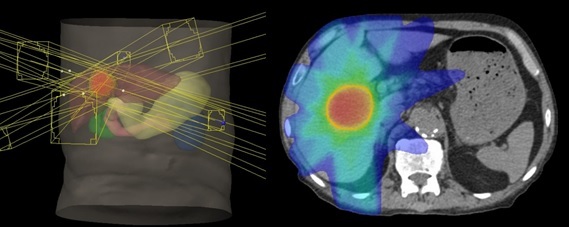

肝がん

肝がんには肝臓から発生した原発性肝がんと、他の部位のがんが肝臓に転移した転移性肝がんに分けられます。原発性肝がんには肝細胞がんと肝内胆管がんがあります。

がんの状態により手術やラジオ波焼灼療法(RFA)、肝動脈化学塞栓療法(カテーテル治療)、薬物療法などを行います。がんが1~3箇所で、これらの治療が困難な場合に体幹部定位放射線治療を行います。

照射線量は40-60Gy、照射期間は1~3週間です。

粒子線治療が望ましい場合は実施施設を紹介致します。

放射線治療に際し消化器内科あるいは外科の診察が必要です。

肝内胆管がん。多方向から腫瘍に対してピンポイントで照射(体幹部定位放射線治療)。